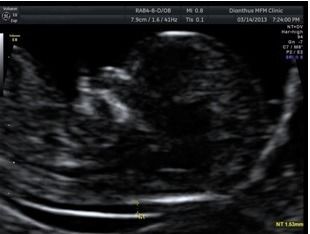

於早期的相關研究中,發現頸部透明帶的增厚與唐氏症,及其他許多染色體異常有高度相關,在後續的研究中,陸續加入的生化指標、以及靜脈導管逆流、三尖瓣逆流、以及鼻骨有無等等軟指標,讓系統的檢出率一路從80%左右提升到93%以上。而且,過程中的不斷發展,近年又加上了可以同時進行子癲前症的篩檢,以及早產評估 。當然,幾近99.5%以上準確率之非侵入性染色體篩檢(NIPS)的發展,則又是另一件事了(這題目請容後再談..)。

如果接受這項檢查,務必要搞清楚自己做的項目內容,以及所擁有的檢測率是很重要的,因為,這牽扯到您個人的風險管理。譬如說,有些院所只測量頸部透明帶加上抽血生化二指標。不做其他的軟指標,則檢測率只有80%,而不是加上靜脈導管逆流、三尖瓣逆流、以及鼻骨有無等等,全部標準量測的93%檢出率,這點,還是一定要搞清楚。

此外,因為畢竟這是源自超音波測量為基礎的檢查,所以再次強調,標準測量是非常重要的(因為很重要,請自己說三遍….),所以超音波儀器的解析度等級以及人員的專業訓練程度就非常重要了,但是很可惜的,目前台灣的醫療環境沒有辦法培養出那麼多的專業團隊。